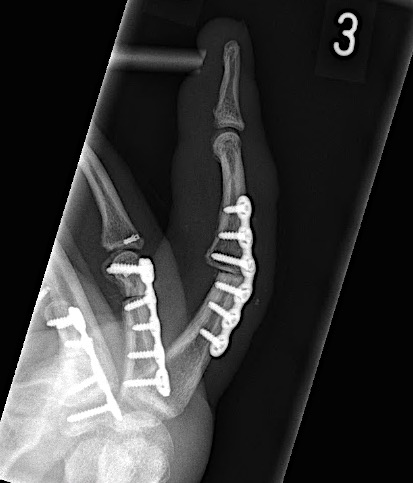

Case 2:

A 20-year-old male suffered a complex multi-digit injury of the right hand requiring revascularization and stabilization of both proximal phalanx and PIP joint fractures (Figs 5 - 8). Multiple plates, including the rotation correction plate from the 1.5 module of the VA Locking Hand System were used for fixation. The Variable Angle Locking system is ideal when only two screws, either proximal or distal, are able to be inserted due to space limitation.

One major advantage of variable angle technology in very distal phalangeal fractures is the ability to be extremely flexible with a wide range of fixation options. Freedom of implant placement assists early mobilization, vital in these complex fractures with associated soft-tissue trauma.